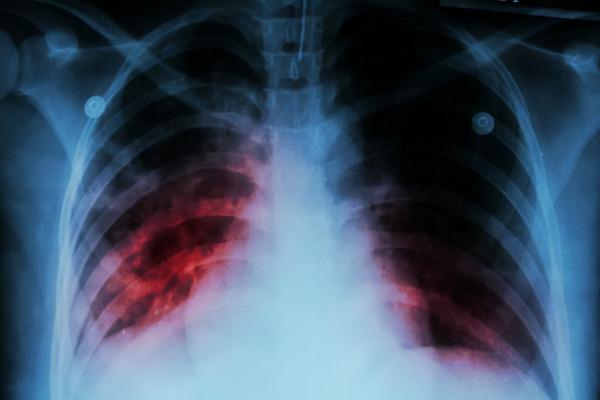

三、肺結核

如果脅肋部位出現疼痛感的時候,患者還伴有反覆咳嗽、胸痛、午後發燒、夜晚盜汗現象,一般與患上肺結核有關。肺結核是一種因為感染了結核桿菌所引起的呼吸系統疾病,有著較強的傳染性。

一旦患上肺結核,患者除了表現出咳嗽、咳痰、胸痛以及盜汗、身體疲乏等症狀之外,炎症還會散播到胸膜部位,導致胸膜受到刺激,就會引起胸部疼痛,以及肋骨部位疼痛現象。

一旦引發了肋骨結核併發症的話,這種脅肋部位疼痛的症狀會特別明顯,並且會伴有咳血的現象。